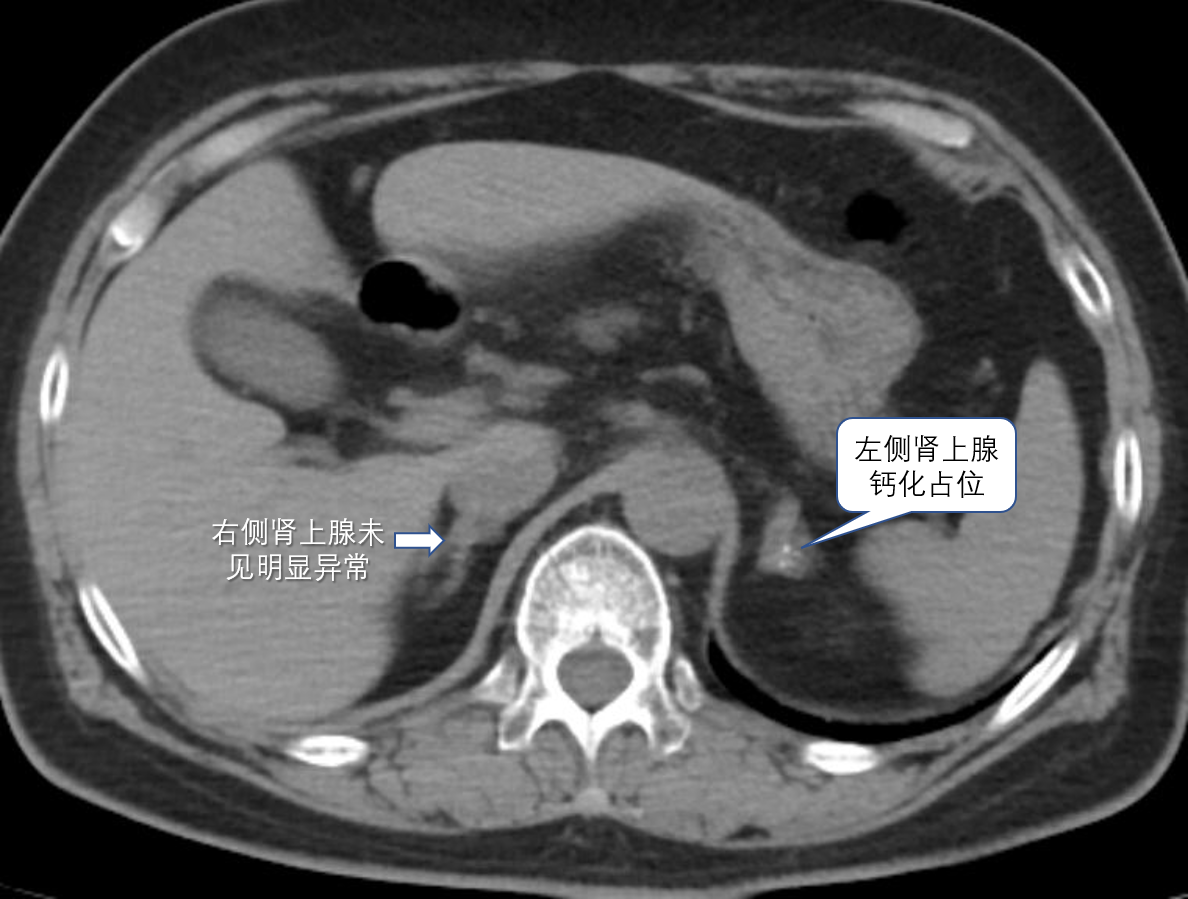

60岁的林阿姨(化名),10前发现血压升高,最高血压到180/100mmHg,反复有头昏不适,通过饮食控制、运动、吃药等多种方式,降压效果时好时坏。直到近期感觉身体乏力、心慌,到家附近捷克论坛 检查发现血钾偏低,血压波动大。当地医生为林阿姨做了一系列高血压的病因筛查。不查不知道,一查吓一跳!医生告诉林阿姨:她得了原发性醛固酮增多症,CT检查还发现她的左侧肾上腺长了一个约28×27mm的瘤,考虑醛固酮瘤导致的高血压,建议行外科行手术切除。

在充分沟通、完善术前评估后,心内科介入团队为林阿姨实施了高难度的双侧肾上腺静脉采血术,手术顺利,成功采血!随后检验科给出的化验结果却出人意料:右侧肾上腺明显异常分泌,而左侧肾上腺(长腺瘤的一侧)无明显分泌。经过与检验科反复核对,结果仍如此,也就是说,从AVS的结果看,她的醛固酮增多并不是CT上看到的那个左侧肾上腺腺瘤引起的。手术直接切除这个瘤,不仅产生手术创伤,而且对血压血钾控制并没有好处。